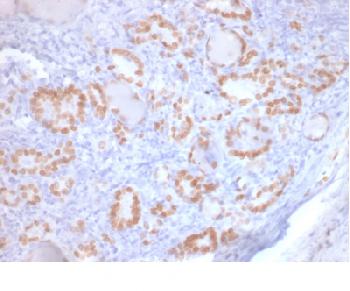

Figure 1: Immunohistochemical analysis of FSH (IHC580) on Pituitary Gland

Follicle-Stimulating Hormone (FSH) allows for progression of ovarian folliculogenesis, and enables Sertoli cell proliferation in the testis. Anti-FSH reacts with FSH-producing cells, therefore FSH staining is useful for classifying pituitary cancers and understanding pituitary disease.

Recommended dilutions: Immunohistochemical analysis: 1:100 - 1:200. However, this need to be optimized based on the research applications.